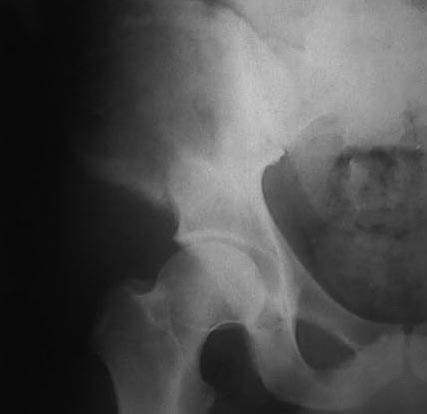

В 2002 году буквально "промелькнул" и исчез пациент с подобным остеолизом. Обследован (биопсия ) в отделении костной онкологии, а затем у дерматологов. Причиной остеолиза признан актиномикоз. К сожалению в то время не удалось выполнить КТ, а рентгенограммы не качественные - в приложении.

Имя     : 18.02.02.jpg

Тип     : image/jpg

Размер  : 30247 байтов

Url     : http://weborto.net:8080/pipermail/ortho/attachments/20110406/5444d703/attachment-0003.jpg